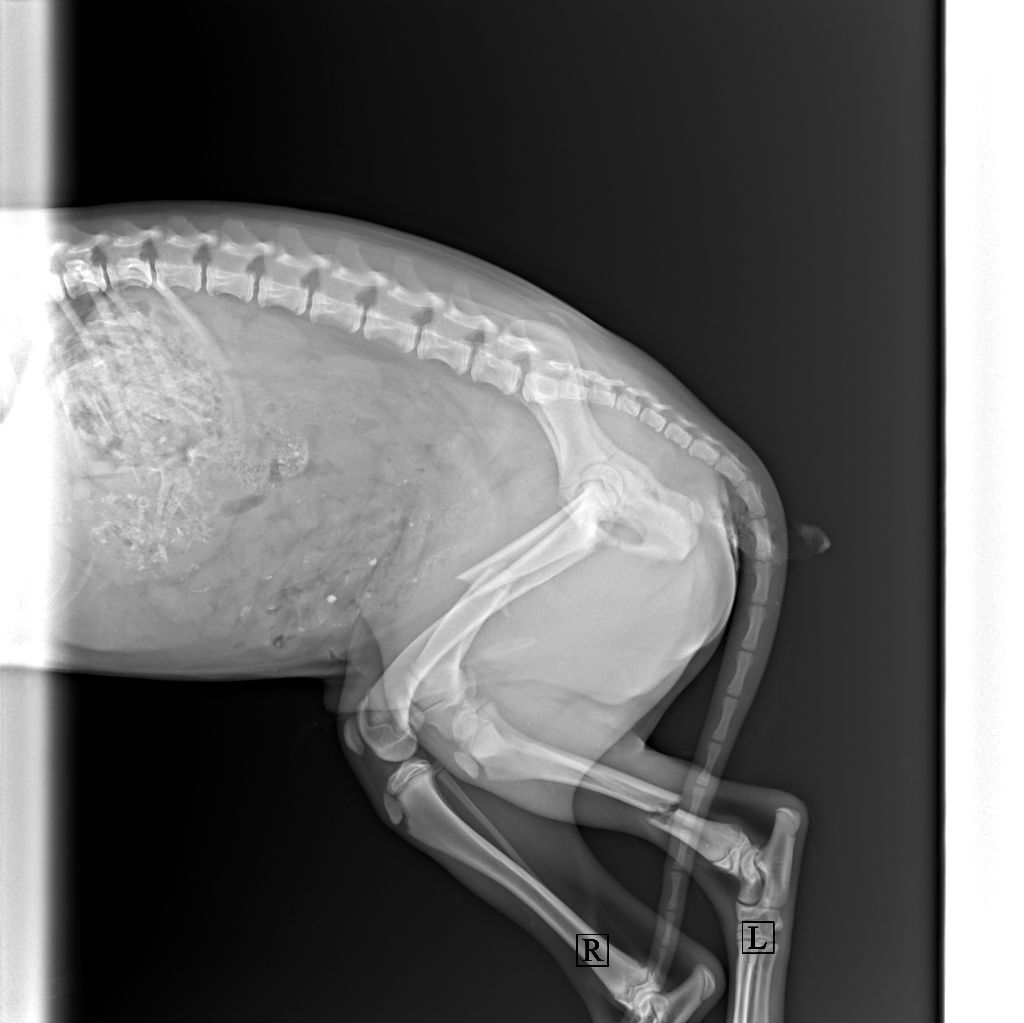

В ветеринарной клинике собаку осмотрели, сделали рентген и врач сообщил сразу о трех серьезных переломах.

Из заключения: "Перелом голени левой тазовой конечности, бедренной кости левой тазовой конечности, плеча левой грудной конечности".

– Врач сообщил, что через несколько дней псу необходима операция. Если ее не сделать, то молодые кости быстро и неправильно срастутся, собака не сможет ходить. Стоимость операции составит 1 000 рублей. Сейчас для меня это большие деньги, я не потяну. Поэтому обращаюсь к читателям АвтоГродно – помогите, – просит Ярослав.